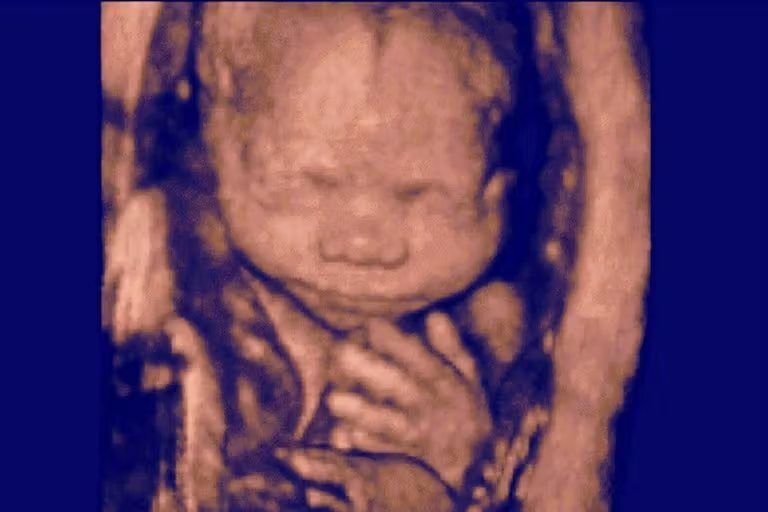

An amniocentesis verified that the baby was not genetically related to the couple. According to the lawsuit, “Ms. Doe and Mr. Doe did not know what to do. They had grown to love this baby, who had already begun kicking. On the one hand, they did not want to lose her even if she was not genetically related to them. On the other hand, they could not imagine carrying a stranger’s baby to term, only to potentially lose her in later legal battles to her biological parents, which would be devastating to the entire family.”

On December 1, 2021, they aborted the baby they claimed to love because they feared the baby’s biological parents might want her.